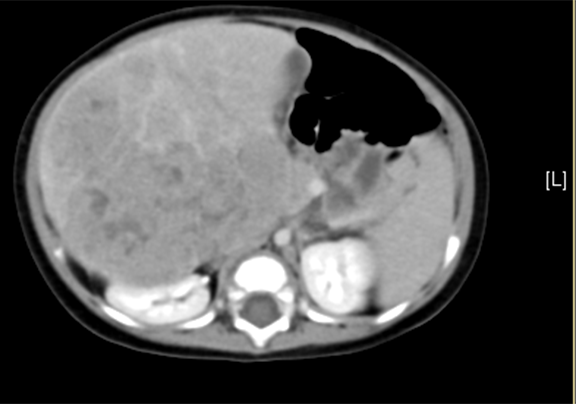

术前CT检查:动脉期

辅助检查: 下腹部增强CT示:考虑肝母细胞瘤可能性大。

查体:腹部膨隆,腹壁静脉未见迂曲扩张,未见胃肠型及蠕动波。腹软,腹部触及一巨大肿物,至右髂窝,约20×15cm大小,质硬,边界不清,活动度差,无压痛、反跳痛,肝脾肋下未及。移动浊音(-),肠鸣音4次/分。